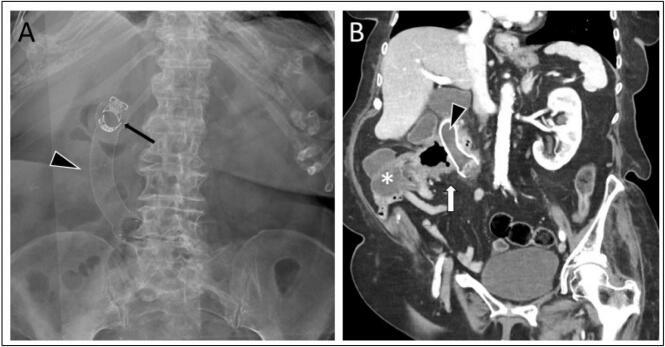

This case report presents a palliative approach involving luminal stent placement via gastroscopy in a patient with non-resectable, locally invasive colorectal cancer, resulting in a malignant duodenocolic fistula.

We discuss different palliative treatment strategies against malignant duodenocolic fistulas, including endoscopic luminal stent placement and specific technical aspects of this procedure, highlighting factors that may contribute to a successful clinical outcome.